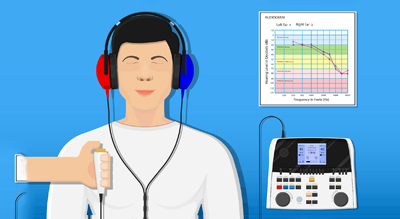

- Audiometry